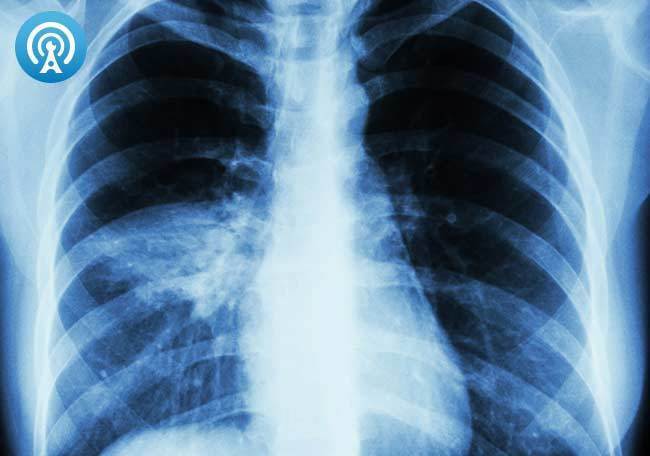

Paciente de 65 años de edad quien acude por presentar fiebre, malestar general y tos con expectoración purulenta.

Paciente en VMI con 7 días de evolución, fiebre de 38° y Rx tórax con opacidad lobular.